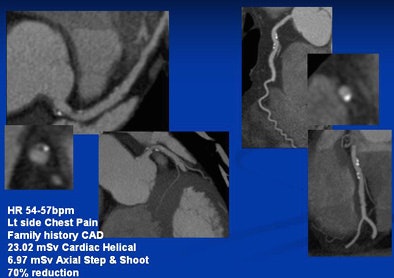

![]() |

| Left main artery and right circumflex artery shows calcified and noncalcified plaque. The CTA dose was reduced from 23.02 mSv with retrospective gating to 6.97 mSv using prospective gating. |

Early cases revealed dose savings of 52% to 74% with the use of prospectively gated rather than retrospectively gated coronary CTA, Dowe said. Savings of 83% and more can be achieved in many patients with further adjustments in technique, such as dialing the kVp down to 100 from 120, which reduces the dose by an additional 38%. The images are indistinguishable.